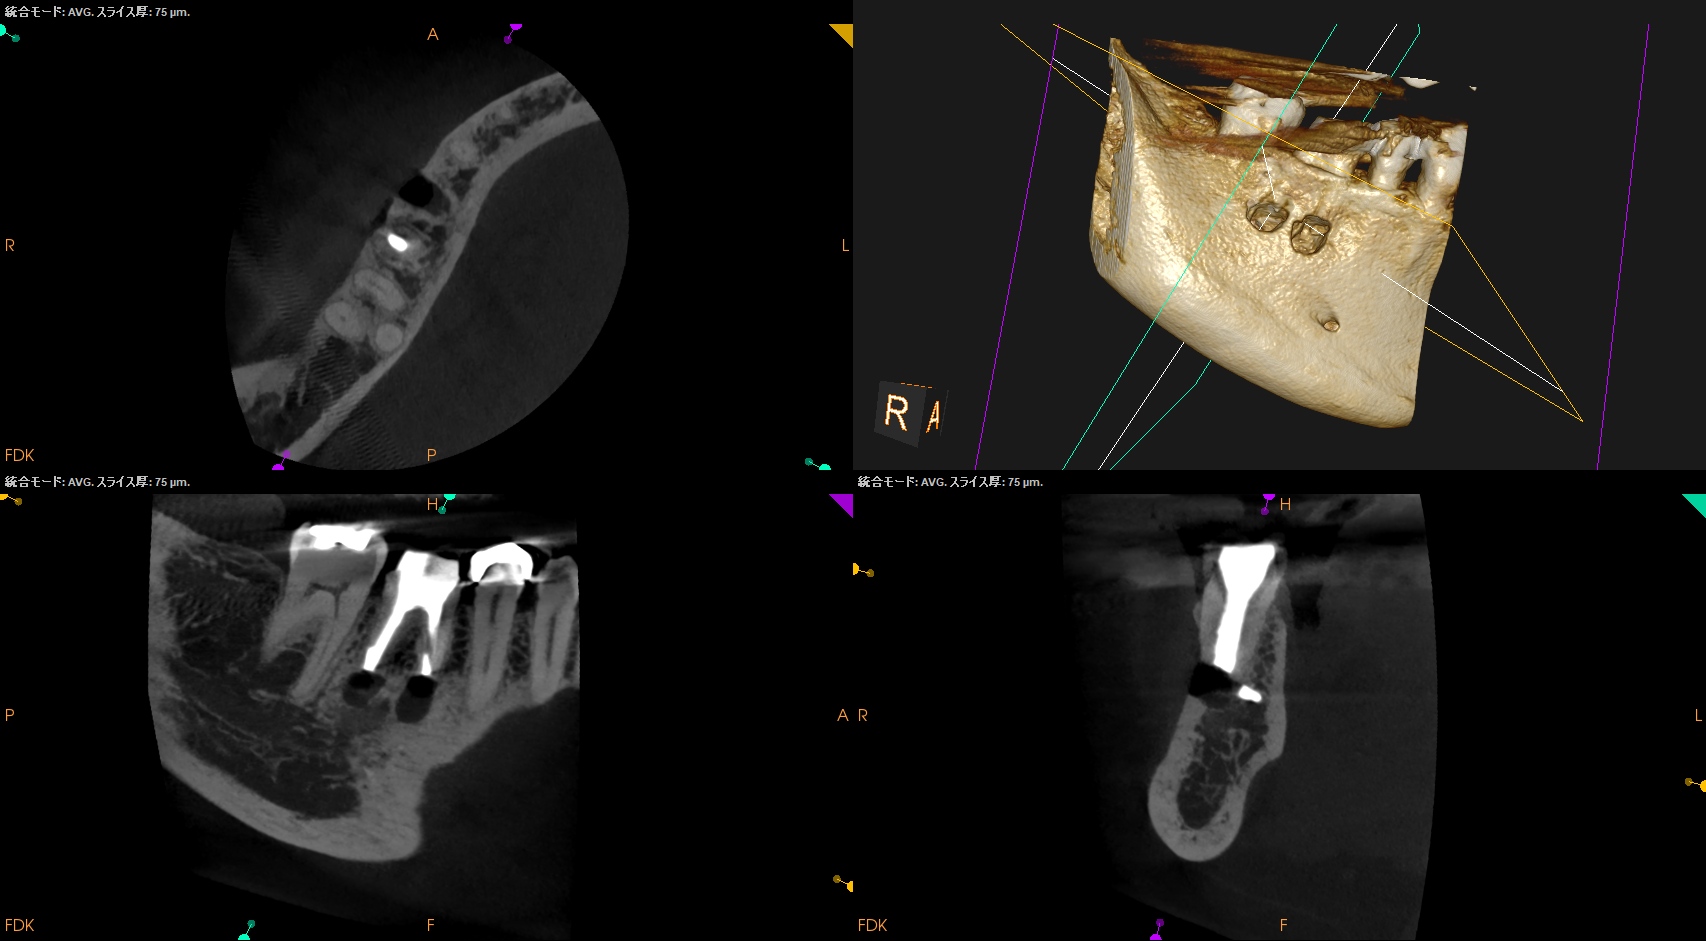

CBCT(2025.12.2)

MB

ML

D

M,Dの根尖部には病変がある。

またMもDも形成・根充が太くなされているので治療は成功率が低いであろう再根管治療ではなくApicoectomyだ。